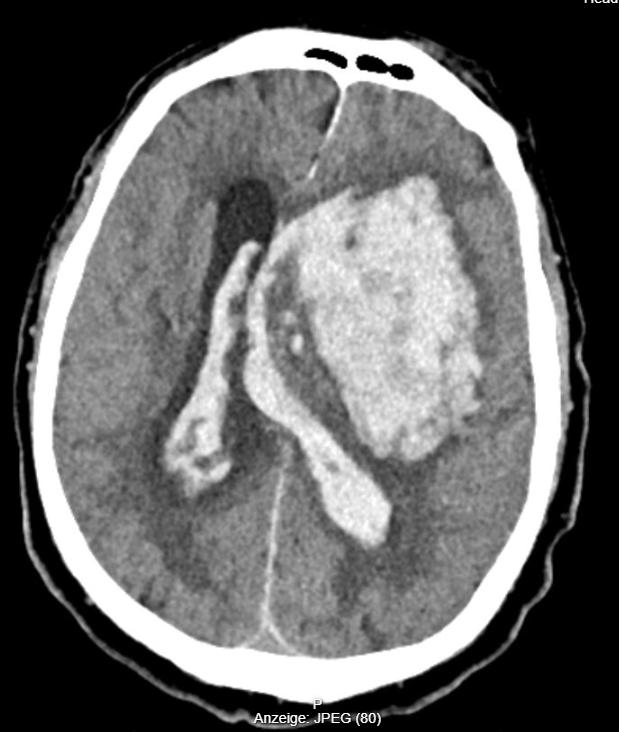

Sollte ein CT erfolgt sein (z.B. Schockraum bei schweren SHT, siehe hier), so können ICP-Anstiege wie folgt darstellbar sein: Herniation, Ventrikelkompression, Mittellinienshift, Verstreichen der Sulci, Verlust der Grau-Weiß-Differenzierung (indirekter Hinweis auf Hirnödem). Hier könnt ihr ein paar Originalbilder aus meiner Tätigkeit begutachten. Beachtet die Kompressions- und Raumforderungsphänomene.